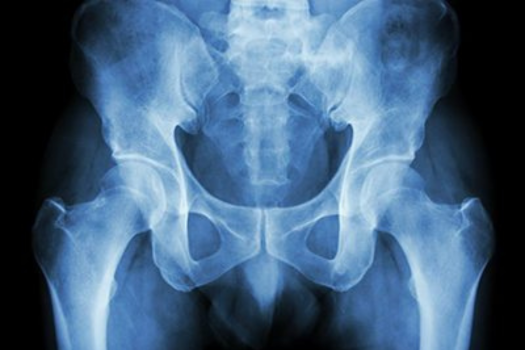

Pete is an orthopaedic trauma surgeon, subspecialising in pelvic, acetabular and lower limb long-bone/periarticular fractures.  His practice is entirely trauma (with a bit of non-union) and his passion is around educating current and aspiring surgeons in fracture care.